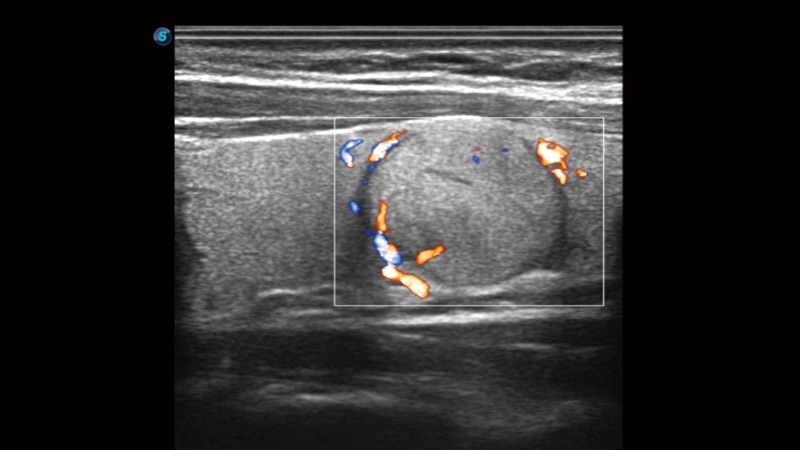

开立医疗通过不断的技术创新,为大众的生命健康提供持续关爱。P12 Plus采用全新一代超声成像平台,新平台旨在将真实还原组织解剖结构作为首要目标。平台采用全新集成化硬件模块,搭载新一代芯片,系统性能得到大幅提升,为您的诊断提供了丰富的临床信息。优异的图像表现,丰富的探头配置,全面的应用功能,为您日常诊断提供了可靠的助手。

凭借开立医疗先进的成像技术和优异的探头技术提供的清晰的图像表现,您可以更自信地做出临床决策。